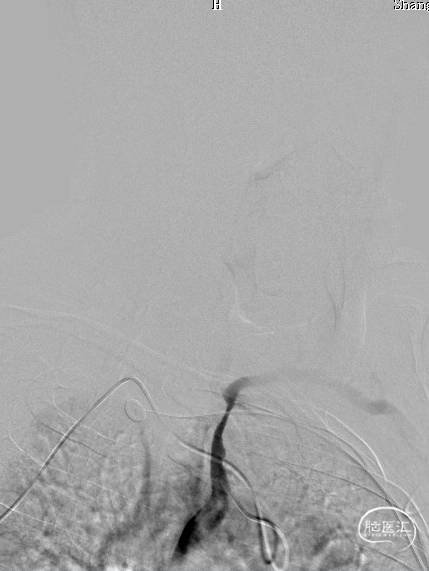

压力泵逐渐加压球扩支架到8atm, 支架打开良好,造影示残余狭窄0%。

双侧锁骨下动脉造影见椎动脉、基底动脉血流通畅,远端未见栓塞表现。

术后头晕呕吐,当日DWI:左侧小脑梗死,MRA未见明显大血管栓塞。